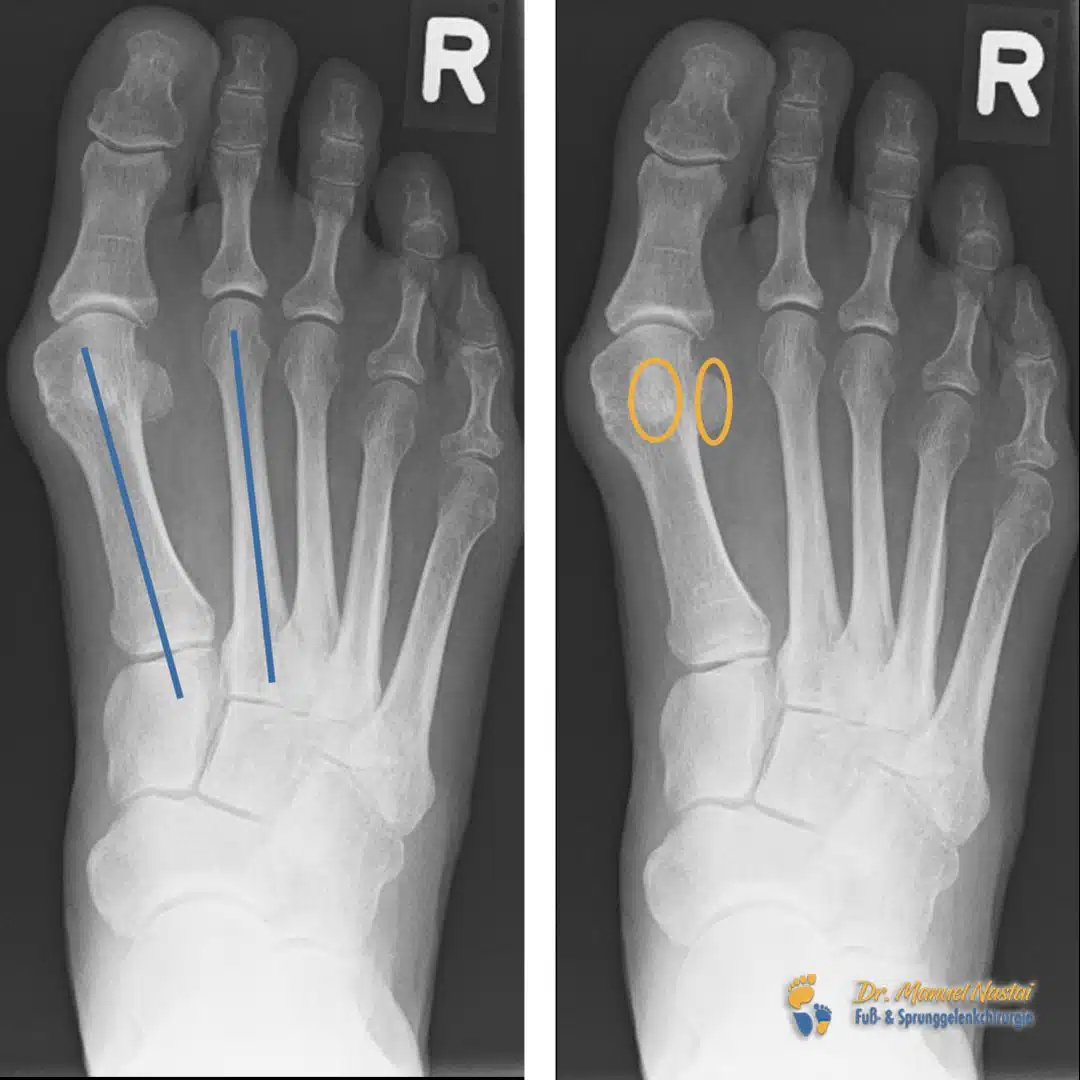

Röntgenbefund präoperativ

Unter Last zeigt sich ein deutlich vergrößerter Intermetatarsalwinkel zwischen dem ersten und zweiten Strahl (IMR1, blau zu kennzeichnen). Dies entspricht einem Metatarsus-primus-varus: Der erste Mittelfußknochen weicht nach medial ab. Gleichzeitig sind die Sesambeine (orange zu markieren) relativ zum ersten Mittelfußkopf lateralisiert und damit nicht mehr zentriert unter dem Köpfchen gelegen.

Die Achsenführung des ersten Strahls ist gestört; die Abweichung lässt sich anhand der eingezeichneten Längsachsen (zentral durch Basis und Köpfchen) gut nachvollziehen. Klinisch erklärt diese Konstellation den schmerzhaften Konflikt im Vorfuß mit Druck über dem Ballen.

Präoperativ: großer IMR1, lateralisiert versetzte Sesambeine, gestörte Achse des ersten Strahls.